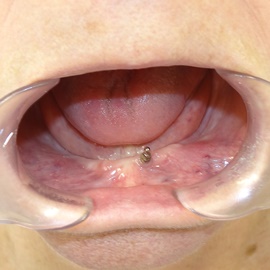

Pacjentka głosiła sie do naszego gabinetu do leczenia z osadzonym mikroimplantem w pozycji lewej dolnej dwójki. Siostrzany implant w pozycji prawej dolnej dwójki wypadł wcześniej, około 1,5 roku od implantacji. Odtworzono przedsionek i dziąsło rogowaciejące, osadzono dwa implanty, jednoczasowo z regeneracją kości. Dopiero na etapie ostatecznej rekonstrukcji protetycznej usunięto zachowany mikroimplant. To się nazywa motywacja do leczenia! Pacjentka przygotowywała sie na ślub prawnuczki :)

Pacjentka lat 58, prowadzi aktywne życie zawodowe. Odczuwała dyskomfort przy użytkowaniu protezy, dodatkowo przy uśmiechu odsłaniała klamry utrzymujące protezę.

Pacjentka lat 68, prowadzi aktywny tryb życia, dużo podróżuje, przeszkadzały jej klamry widoczne na zębach przy uśmiechu, oraz słaba stabilność protezy, co powodowało dyskomfort przy użytkowaniu.

Pacjentka prowadzi aktywne życie zawodowe, niedawno zakończyła leczenie ortodontyczne, niestety nie nastąpiło po nim właściwe leczenie protetyczne. Użytkowała protezę ruchomą z klamrami dziąsłowymi.

Hybrydowe podparcie protezy ruchomej na jednym implancie i jednym własnym zębie. Nie zawsze możemy osadzić u pacjenta dwa implanty. Przykłady hybrydowego podparcia protezy ruchomej na atachmentach opartych na własnym zębie i implancie.